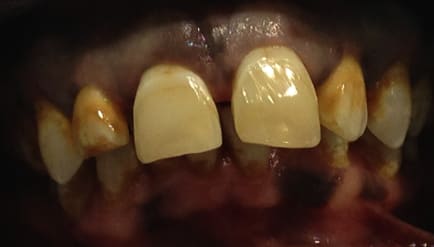

-Teinte "orange" sur la moitié cervicale , le patient me dit que petit l'eau de son village était très fluorée.

C'est pris en vitesse avec mon iphone .

érosion infiltration , je suis pas contre mais j'ai des doutes dessus .J'ai lu quelques articles , on pouvait masquer quelques taches blanches avec des résultats pas toujours parfaits.

C'est un cas de fluorose...